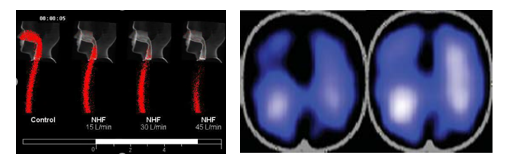

研究表明,只有经鼻塞输送给患者的高流量气体,才能明显减少上气道死腔内重复呼吸的气体,从而起到“生理死腔冲刷效应”,同时产生一定的“呼气末正压效应”,增加呼气末的肺容积。

因此虽然我们在临床中有时也会给使用高流量装置连接喉罩、面罩、T管等,但这样的连接方式,更主要保证的是提供给患者是“恒定氧浓度”、“充分温湿化”的气体,这样的气体未经鼻塞输送给患者,是无法充分达到经鼻高流量氧疗的相应生理学效应的。